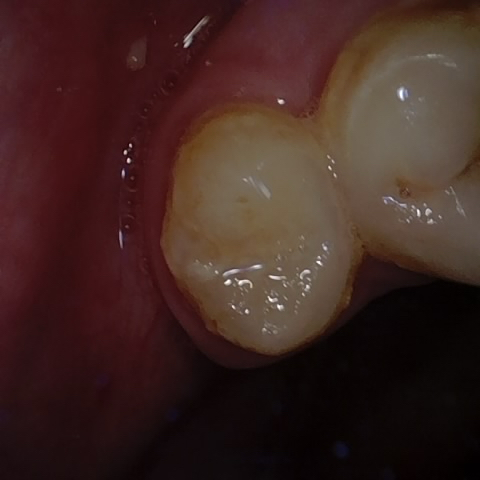

Annotated as "Good"